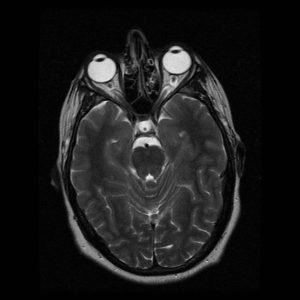

Our specialists conduct a detailed eye and nerve assessment using advanced diagnostic tools like OCT, visual field analysis, fundus imaging, and neuroimaging support. We evaluate conditions such as optic neuritis, optic neuropathy, papilledema, eye movement disorders, and visual field defects, ensuring an accurate diagnosis that guides the best treatment approach.

Step 1: Comprehensive Neuro-Ophthalmic Assessment – Using advanced diagnostic tools such as OCT, visual field analysis, fundus imaging, and neuroimaging support, we evaluate conditions like optic neuritis, optic neuropathy, eye movement disorders, and papilledema to plan precise treatment.

Advanced Diagnostics & Imaging – For detailed assessment using OCT, visual fields, and MRI/CT referrals.